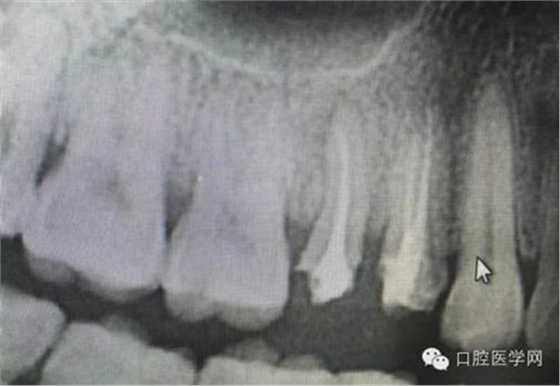

根管再治療是我們比較頭疼的,尤其是那些冠修復(fù)過(guò)的,我們有很多的麻煩需要去溝通,比如可能導(dǎo)致的側(cè)穿、可能沒有看到的腐質(zhì)、可能導(dǎo)致的崩瓷,或者是后期可能出現(xiàn)冠折......這些需要我們和患者好好的溝通。全瓷冠還好些,金屬冠根測(cè)的時(shí)候很是麻煩,總之我們做修復(fù)的時(shí)候不要單純的追求速度,追求效益,適當(dāng)?shù)淖⒁庀挛覀兊幕A(chǔ)治療和設(shè)計(jì)。

根管治療,我們?cè)诖髮W(xué)的時(shí)候就學(xué)習(xí)的東西,標(biāo)準(zhǔn)就在那里放著,可是很多時(shí)候我們熟視無(wú)睹,放任我們的想象去做。我們多些重視,多些心思,會(huì)好很多,認(rèn)真對(duì)待每顆牙齒。